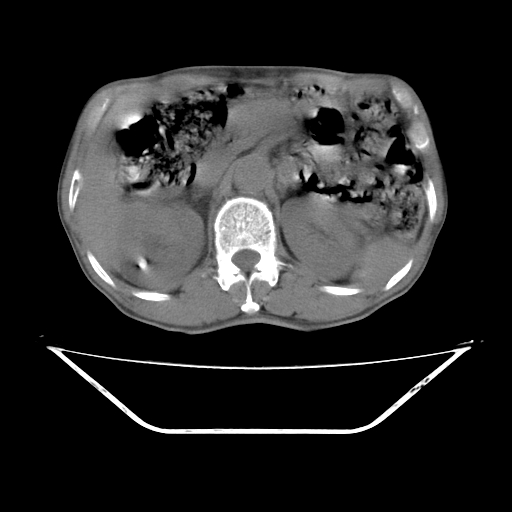

平扫

考虑右肾盂癌,肾动脉受侵,右肾功能减退,右肾盂输尿管积水,管壁增厚,考虑种植转移,应该把下面扫完的

支持右侧肾盂癌伴肾静脉瘤栓形成可能性大,右肾结石.肝右叶后段低密度影,不除外转移.

考虑右肾盂癌,肾动脉受侵,右肾功能减退,右肾盂输尿管积水,管壁增厚,考虑种植转移  支持

考虑右侧肾盂癌。右侧输尿管扩张未扫描完。

右肾盂旁ca并肾静脉瘤栓形成/肾功能降低。

右肾结石。

右肾盂癌,肾动脉受侵,右肾盂输尿管积水,管壁增厚,考虑种植转移

右肾盂移行细胞癌并右输尿管中段转移.肾积水.

支持 右侧肾盂癌伴肾静脉瘤栓形成可能性大,右肾结石;肝右叶后段低密度影,不除外转移。

1.右侧肾盂癌伴肾盂积水。

2.肾脏功能减退,原因有:(1)肾动脉受侵。(2)肾静脉受侵(3)肾积水,等。本例,肾动脉显影较好,但受压明显;肾静脉无明显显示,受压或静脉癌栓,下腔静脉腔内未见明显充盈缺损。

3.右侧上段输尿管扩张,原因:(1)积水所致;(2)种植。